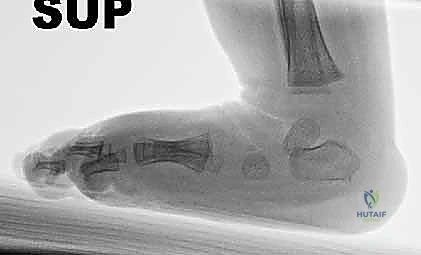

بعد الولادة، يتم التشخيص بالفحص السريري المباشر. لا حاجة عادة للأشعة السينية (X-rays) للأطفال حديثي الولادة لأن عظامهم لا تزال غضروفية ولن تظهر بوضوح في الأشعة.